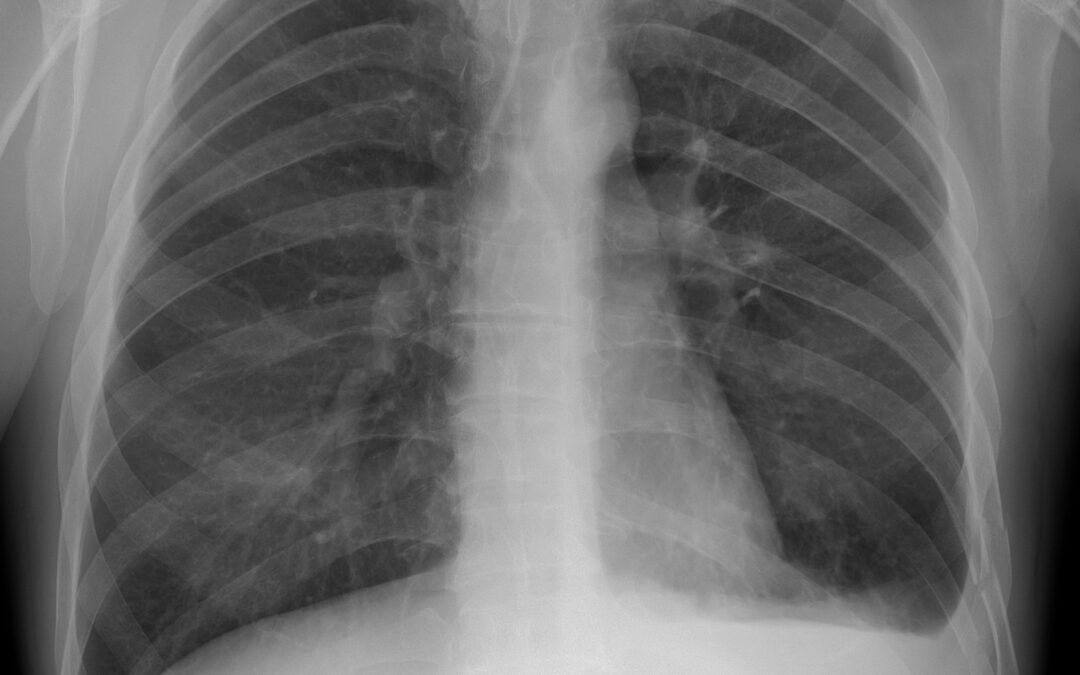

Hollywood Diagnosticss Center is proud to share the recent news that lung cancer detection and even radiologist’s performance will get a boost from an artificial intelligence (AI) algorithm that pinpoints previously un-detected cancers on chest X-rays. In a...